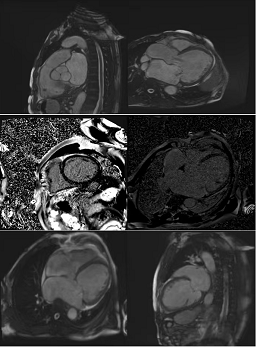

入院检查:甲状腺功能、凝血功能、血常规、hs-CRP均正常范围,eGFR 71ml/min/1.73㎡,BNP 3881.7pg/ml ,肝功能“TBIL 41.2umol/L DBIL 17.1 umol/L IBIL 24.1umol/L”;心电图提示“异位心律,心房颤动,偶发室早,QRS 波宽度113ms”;心超提示“扩张型心肌病 ,全心扩大(左房内径 64mm,左心室舒张末期内径82.1mm),左室壁运动弥漫性减低,二尖瓣中度反流,三尖瓣轻度反流,主动脉瓣轻-中度反流,心律失常,左室收缩功能减低(LVEF 37%)”;心肌MR提示“扩张型心肌病,全心扩大,LVEF 22.4%,左心室基底段-中央段间隔壁心肌中层见点、线样延迟强化”;动态心电图“心房颤动24小时总心搏114767次,平均90次/分,最慢67次/分,最快164次/分,多源室早(1918次,包括单发室早1854次,成对28对,短阵室速2阵)”。

心肌磁共振